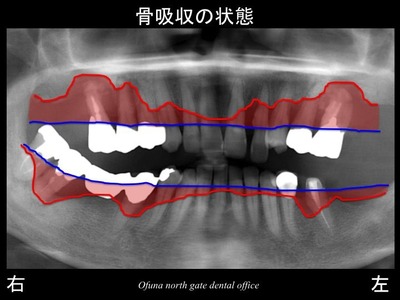

いつものように 骨吸収の状態を分かりやすくするために

骨吸収の状態を線で書いたのが以下のレントゲンになります。

青線が骨吸収を起こす前の骨の位置です。

赤線は、現在の骨の位置です。

かなりの骨吸収が起こっているのが分かるかと思います。

さらに わかりやすくするために、

骨吸収部位を赤色で表示します。

非常に骨吸収が大きいのが分かるかと思います。